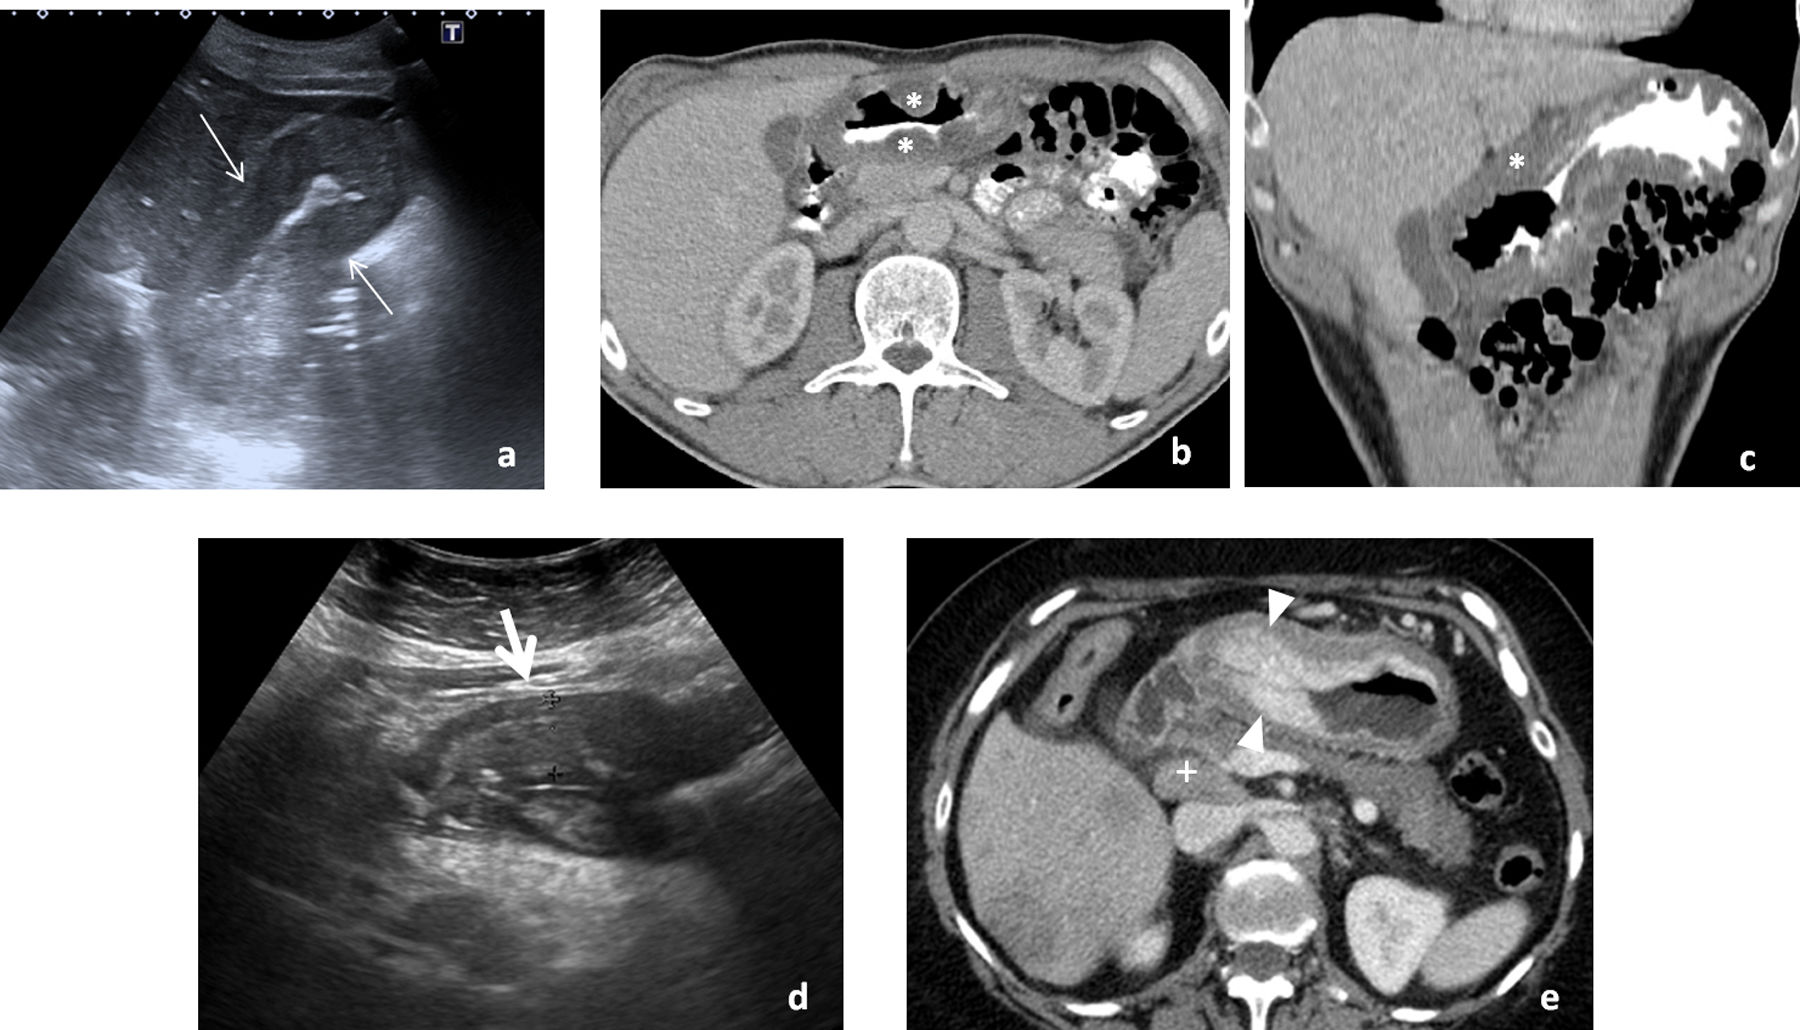

Consecuencia de la ingesta de la larva del parásito en pescado crudo o poco cocinado; aunque los primeros casos se describen en países asiáticos, se ha globalizado. Cuando, como ocurre habitualmente, afecta al estómago, la sintomatología aparece en menos de 24 horas. Provoca intenso dolor agudo en epigastrio, náuseas y vómitos, pudiendo simular patología pancreatobiliar. La ecografía, muchas veces urgente, muestra un importante engrosamiento difuso de la pared gástrica (fig. 1A) y ascitis, planteando diagnóstico diferencial con patología tumoral (linfoma o adenocarcinoma difuso) o gastritis eosinofílica (fig. 1B).

Afectación infecciosa del estómago. A-C) Primer caso de paciente que acude a urgencias por dolor intenso en epigastrio, con náuseas y vómitos abundantes de pocas horas de evolución, por el que se solicita ecografía urgente (A). Engrosamiento circunferencial y simétrico (flechas finas) de la pared de cuerpo y antro gástrico, que se correlaciona con las imágenes de tomografía computarizada (TC) en incidencia axial (B) y reconstrucción coronal (C) que se realizó a continuación, donde predomina un engrosamiento hipodenso (*) que orienta a edema submucoso. Con la sospecha de cuadro inflamatorio sin poder descartar otras causas, el paciente es sometido a endoscopia que muestra engrosamiento de pliegues gástricos y eritema mucoso con el resultado histológico en la biopsia de gastritis crónica superficial con eosinofilia, muy sugerente de gastritis por anisakis, aunque no pudo identificarse el parásito. El cuadro se resolvió en pocos días con tratamiento sintomático. D y E) Segundo caso de paciente que refiere dolor epigástrico de semanas de evolución con vómitos ocasionales. Se solicita ecografía como prueba de estudio inicial, que muestra un engrosamiento de la pared del antro gástrico, asimétrico, más marcado en la pared anterior (flecha gruesa), sospechoso de origen tumoral (D). La TC realizada posteriormente (E) presenta un hallazgo similar, mostrando una captación irregular de contraste (cabezas de flecha) de la mucosa gástrica, con una adenopatía prominente por delante de la vena cava inferior (+) sospechosa de diseminación ganglionar. La endoscopia y biopsia posterior confirman el diagnóstico de adenocarcinoma.